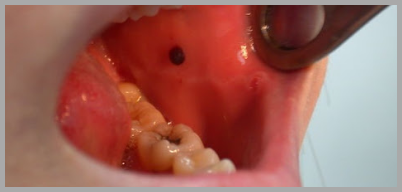

두번째로 소개해드릴 입안 피멍울 원인은 세균에 의한 감염 입니다. 1번 항목과 공통적인 부분이라 할 수 있습니다. 하지만 입안에 정상적으로 존재하는 세균이 아니라 감염을 일으키는 세균에 의해 입안 피멍울이 발생한다면 전문적인 치료를 요할 수 있습니다. 특히 성병을 일으키는 헤르페스의 경우 입안 염증도 일으킬 수 있습니다. 이를 위해서는 꾸준한 양치질과 가글 등이 도움이 될 수 있습니다. 하지만 양치 직후 가글액을 사용하시면 치아 변색을 유발하실 수 있다는 점 주의하세요.

자주 발생하는 입안 피멍울의 경우 다른 원인이 있을 수 있습니다. 피부의 이상이거나 치아 및 잇몸의 이상일 수 있습니다. 이 경우 치과를 방문해보시는 것을 추천드립니다. 혹은 주변에 치과가 없으시다면 피부과의 도움을 받으실 수도 있습니다. 시중의 소염제나 기타 일반의약품으로 자가 치료를 하실 경우 골든타임을 놓쳐 악화될 수도 있다는 점을 유념하시기 바랍니다.